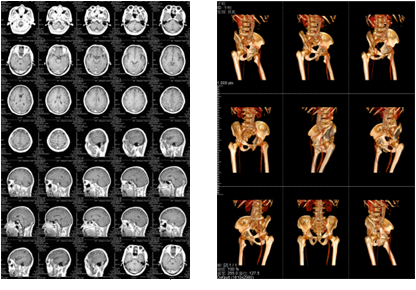

該三甲醫(yī)院放射科負(fù)責(zé)日常CT、核磁共振影像的輸出,平均的日打印量在1000張左右。在導(dǎo)入解決方案前,該放射科的影像輸出使用干式膠片打印傳統(tǒng)膠片,輸出設(shè)備價格不菲,而且傳統(tǒng)膠片價格更是高昂。另外,傳統(tǒng)膠片不能實現(xiàn)彩色輸出,醫(yī)生必須在背光板上進(jìn)行診斷,膠片本身還含有重金屬等有毒物質(zhì),污染環(huán)境。為此,柯尼卡美能達(dá)向?qū)I(yè)供應(yīng)商采購了DICOM轉(zhuǎn)換服務(wù)器和符合醫(yī)院要求的打印膠片紙,可實現(xiàn)三維打印,打印的影像可直接在自然光下觀看,便于醫(yī)生診斷;膠片紙的成本是傳統(tǒng)膠片的三分之一而且不含毒物質(zhì),既節(jié)省成本又綠色環(huán)保。

膠片紙輸出樣張示意